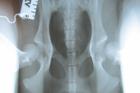

PENN-HIP SCORING

Our vet Kevin Camilleri is qualified and accredited to take Penn-Hip x-rays and submit them for a special type of scoring based on joint laxity(distraction index of DI) which has been found to be one of the main causes of hip dysplasia in dogs. This examination can be carried out as early as five months of age in suitable breeds as the distraction index remains largely the same throughout the animal's lifetime. More information can be obtained from the practice or directly from the following site: http://info.antechimagingservices.com/pennhip/